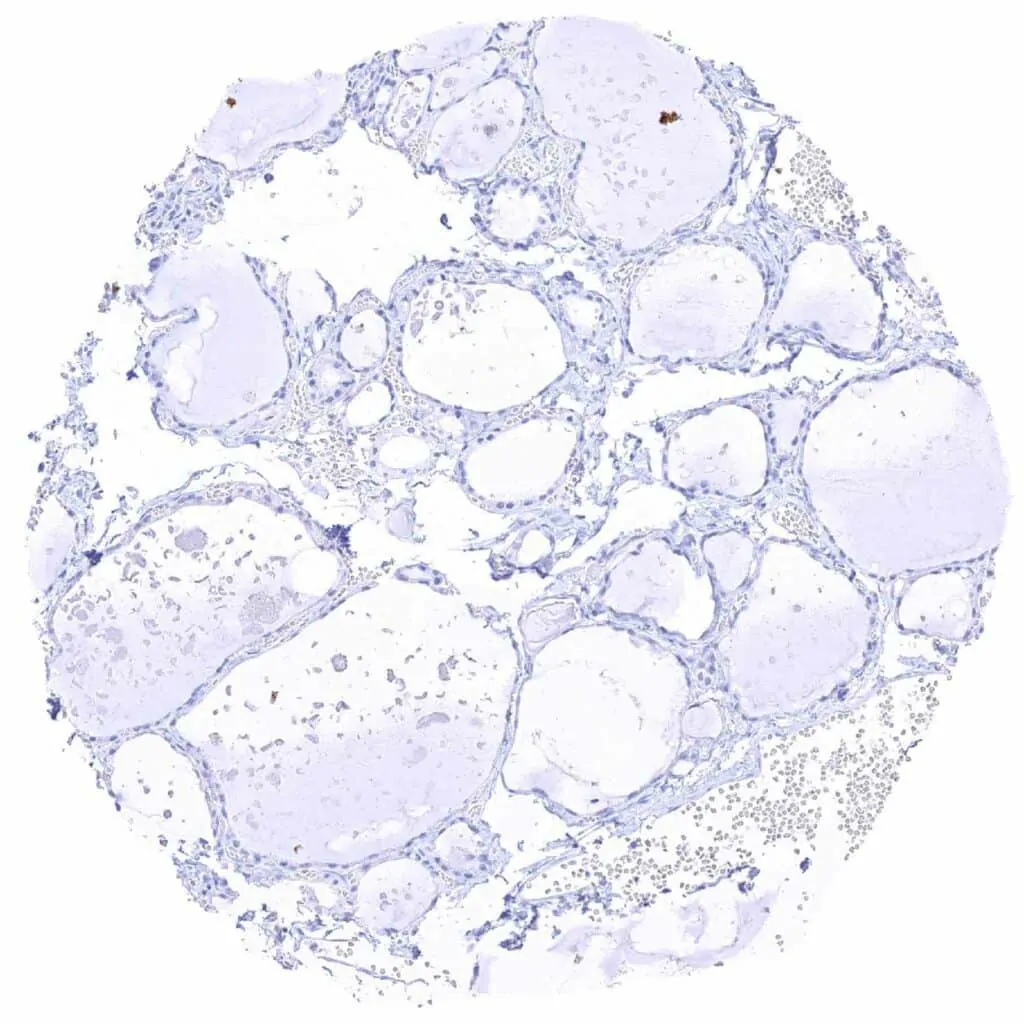

Thyroid gland